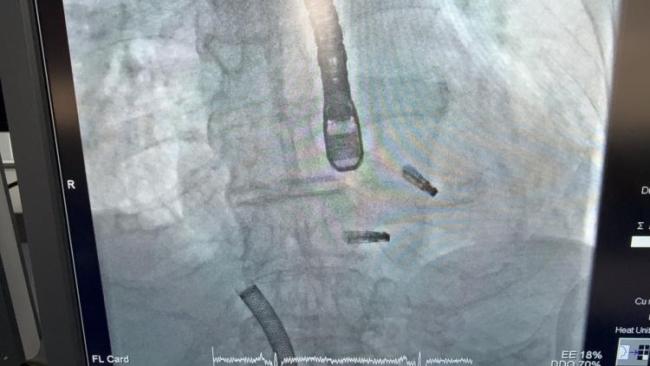

84岁的李老先生,数月前因胸闷不适来到上海市东方医院,诊断为“急性冠脉综合征、非ST段抬高心肌梗死”。冠脉造影发现回旋支近段完全闭塞,医生紧急为他植入支架,成功开通血管。当时的心脏超声已显示他有“中重度二尖瓣反流、重度三尖瓣反流”,但考虑到他刚做完支架手术,医生希望先通过规范的药物治疗来稳定瓣膜反流情况,再评估是否需要介入干预。